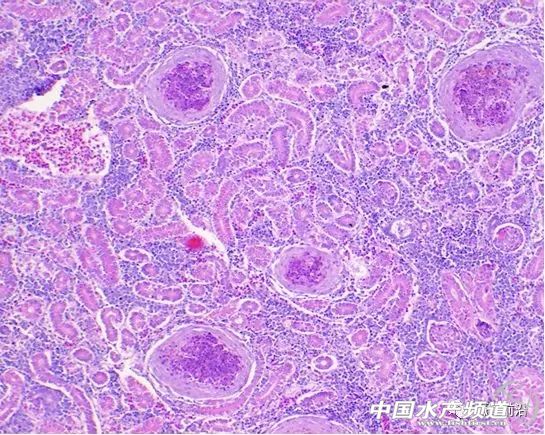

| 中國(guó)水產(chǎn)頻道原創(chuàng)報(bào)道, 加州鱸諾卡氏菌病防治技術(shù)探討 整理/ 鱖鱸前沿 李曉欣 本文整理自鱖鱸前沿第6期公開(kāi)課《加州鱸諾卡氏菌病防治技術(shù)探討》,課程嘉賓是廣州利洋水產(chǎn)科技股份有限公司廣佛區(qū)域經(jīng)理杜德群,長(zhǎng)按識(shí)別下方圖片二維碼可回顧本期課程。 加州鱸魚(yú)屬于鱸形目,鱸形目包括海鱸、生魚(yú)等是諾卡氏菌感染率較高的主要養(yǎng)殖品種。加州鱸是閉鰾類,鰾不完整,生活于中下層和底層,適合高密度養(yǎng)殖,耐低氧,不耐高氧,對(duì)氣體變化非常敏感,易得氣泡病(氧氣和氮?dú)猓?/div> 加州鱸爛身(潰瘍)病分為3大類:普通型爛身(氣單胞菌型)、膿瘡型爛身(諾卡氏菌型)及病毒型爛身(蛙虹彩病毒)。 普通型爛身 普通型爛身以氣單胞菌感染引起,病癥表現(xiàn)為爛身、爛鰭、爛嘴、爛眼、爛鰓等,發(fā)病初期可急性發(fā)生(以敗血癥為主),后轉(zhuǎn)為慢性(潰瘍),也可直接慢性發(fā)生。 魚(yú)體發(fā)生潰爛的前提是魚(yú)體有傷口,繼而感染到細(xì)菌引發(fā)潰爛。從實(shí)際的養(yǎng)殖生產(chǎn)來(lái)看,造成魚(yú)體受傷的原因主要如下: 1、氣泡病。實(shí)際中較多是由氣泡病造成的魚(yú)體受傷,這是鱸形目的魚(yú)受傷的重要誘發(fā)因素。 2、拉網(wǎng)。拉網(wǎng)過(guò)程中操作不當(dāng)會(huì)造成魚(yú)體受傷,從而繼發(fā)感染。 3、水變。水變之后魚(yú)體會(huì)出現(xiàn)鱗片脫落或爛尾等,緊接著就開(kāi)始爛身、爛嘴等等。 4、寄生蟲(chóng)。甲殼類寄生蟲(chóng)如錨頭蚤、魚(yú)虱等寄生,造成魚(yú)體受傷。 處理建議 普通型爛身的處理比較簡(jiǎn)單,急性的以氣泡病為主,急性死亡一般是氣泡病加重的,慢性的就按照細(xì)菌病處理。 細(xì)菌病處理可外用刺激性小的消毒劑,低劑量、間隔多次使用,以防反復(fù);內(nèi)服抗菌藥,這關(guān)鍵在于魚(yú)的吃料情況,如果魚(yú)吃料好,那么處理效果就好。 膿瘡型爛身 膿瘡型爛身是以諾卡氏菌感染引起,病癥表現(xiàn)為尾鰭、胸鰭基部,鰓蓋內(nèi)側(cè)等處潰爛、化膿,腎、脾、心臟等內(nèi)臟常有白點(diǎn),魚(yú)體缺乏維生素B時(shí)易發(fā)生,為慢性發(fā)生。如果池塘感染過(guò)諾卡氏菌,那么這個(gè)菌在池塘將會(huì)存活9年之久,最好要徹底清塘、清淤。 諾卡氏菌感染的病魚(yú)在體表有鰓結(jié)節(jié)型和軀干結(jié)節(jié)型兩類表現(xiàn)型: 1、軀干結(jié)節(jié)型 主要表現(xiàn)為軀干部的皮下脂肪組織和肌肉發(fā)生潰瘍,在外觀上則膨大突出成為許多大小不一、形狀不規(guī)則的結(jié)節(jié),剖開(kāi)結(jié)節(jié)后流出白色或稍帶紅色的濃汁,心臟、脾臟、腎臟、鰾等也有結(jié)節(jié),所有病灶處都有炎癥。 2、鰓結(jié)節(jié)型 主要表現(xiàn)為在鰓絲基部形成乳白色的大型結(jié)節(jié),鰓明顯褪色。多數(shù)發(fā)生在低溫期,廣東一般進(jìn)入到10月中下旬會(huì)出現(xiàn)這種情況。 在普通培養(yǎng)基上面分離諾卡氏菌,常溫條件下(25-28℃)需要10天以上,溫度稍高一點(diǎn)可能要7天,即諾卡氏菌最少需要一周才能從培養(yǎng)基上生長(zhǎng)出來(lái)。 諾卡氏菌 所以說(shuō)諾卡氏菌病是慢性病,這意味著如果魚(yú)塘出現(xiàn)大批量死亡,檢測(cè)發(fā)現(xiàn)很多魚(yú)已經(jīng)感染諾卡氏菌,這時(shí)一定不是諾卡氏菌造成的死亡,而可能是魚(yú)體感染諾卡氏菌后體質(zhì)弱,氣候環(huán)境變化、“三殺一消”、缺氧、氣泡病、繼發(fā)或并發(fā)氣單胞菌、寄生蟲(chóng)感染、病毒發(fā)作等導(dǎo)致死亡量猛增,大家在處理這個(gè)病害時(shí)不要糾結(jié)于諾卡氏菌,這是很重要的一個(gè)關(guān)鍵點(diǎn)。 肝臟 頭腎 后腎 脾臟 有養(yǎng)殖戶會(huì)疑問(wèn),諾卡氏菌是從哪里來(lái)的?實(shí)際上應(yīng)該是從冰鮮魚(yú)帶入,最早諾卡氏菌是從海水魚(yú)發(fā)現(xiàn)的。近幾年的走訪來(lái)看,四川、貴州一帶諾卡氏菌的發(fā)病率很低,當(dāng)?shù)乇r養(yǎng)殖比例很小,江浙一帶發(fā)病率高,廣東發(fā)病率也是比較高,尤其在2007-2010年期間發(fā)病非常厲害。 2008年左右佛山很多養(yǎng)殖戶還不認(rèn)識(shí)這個(gè)病,當(dāng)時(shí)把白點(diǎn)叫做孢子蟲(chóng),直到2012-2013年觀念才慢慢開(kāi)始轉(zhuǎn)變,但目前也有很多人還認(rèn)為它是孢子蟲(chóng)。在這里需要糾正一點(diǎn),目前加州鱸魚(yú)暫時(shí)還沒(méi)有發(fā)現(xiàn)孢子蟲(chóng)感染的情況,實(shí)際上孢子蟲(chóng)對(duì)于鱸形目的魚(yú)不是太敏感,所以大家在這方面不要有誤區(qū)。 治療方法 諾卡氏菌病的治療難度較大,目前還沒(méi)有能把諾卡氏菌完全抑制住的藥物,而殺菌力強(qiáng)的藥物毒性、副作用也非常大,建議大家選擇藥物時(shí)要慎重。諾卡氏菌是革蘭氏陽(yáng)性菌,治療上可內(nèi)服抗革蘭氏陽(yáng)性菌的藥物,如氟苯尼考、阿莫西林、硫酸新霉素等有一定抑菌效果,但無(wú)法徹底根治,同時(shí)注意耐藥性。 預(yù)防措施 1、防受傷:氣泡病是引起鱸魚(yú)受傷的重要原因,另外拉網(wǎng)、分池、分塘等也容易引起魚(yú)受傷,要注意預(yù)防。 2、補(bǔ)充維生素:養(yǎng)殖過(guò)程當(dāng)中要勤補(bǔ)充維生素,特別是從冰鮮魚(yú)轉(zhuǎn)向膨化飼料以后,膨化料里的維生素特別是維生素B族要多補(bǔ)充。 3、防繼發(fā)感染:可每隔7到10天左右拋網(wǎng)檢測(cè)魚(yú)體有沒(méi)有寄生蟲(chóng)、細(xì)菌等感染。 諾卡氏菌感染是慢性病,死亡率不會(huì)太大,幾條或十條,當(dāng)池塘魚(yú)出現(xiàn)小規(guī)模死亡時(shí)是本身病的問(wèn)題;但如果池塘魚(yú)出現(xiàn)大規(guī)模的死亡,幾十、上百甚至過(guò)千條,就不是本身病的問(wèn)題,而可能是魚(yú)體感染諾卡氏菌后體質(zhì)弱,氣候環(huán)境變化、“三殺一消”、缺氧、氣泡病、繼發(fā)或并發(fā)氣單胞菌、寄生蟲(chóng)感染、病毒發(fā)作等導(dǎo)致死亡量猛增,所以一定要分析清楚病程,而不要在諾卡氏菌本身這個(gè)問(wèn)題上太過(guò)糾結(jié)。 實(shí)際上,加州鱸諾卡氏菌病還是防重于治,因?yàn)楹芏嘣谥委煏r(shí),魚(yú)發(fā)病后已經(jīng)不吃食了。由于地區(qū)、養(yǎng)殖模式等不同,加州鱸魚(yú)的諾卡氏菌發(fā)病的程度也不一樣,建議大家根據(jù)當(dāng)?shù)仞B(yǎng)殖模式、放養(yǎng)密度等針對(duì)性處理。 互動(dòng)交流實(shí)錄 01、諾卡氏菌主要是什么原因?qū)е碌哪兀?/b> 杜德群:諾卡氏菌本身就是一個(gè)細(xì)菌,最早是發(fā)生從海水魚(yú)上分離到的,所以冰鮮魚(yú)是一個(gè)非常重要的傳染源。需要強(qiáng)調(diào)的一點(diǎn)是,諾卡氏菌的核心問(wèn)題還是魚(yú)體受傷,如果魚(yú)體不受傷,諾卡氏菌是沒(méi)有機(jī)會(huì)感染魚(yú)的。另外,實(shí)際上很多病都是病從口入的,建議大家勤預(yù)防,多補(bǔ)充一些維生素,增強(qiáng)魚(yú)的體質(zhì),包括抗病力、抗低氧、抗應(yīng)激能力。 02、諾卡氏菌病具體怎么處理? 杜德群:對(duì)于細(xì)菌病,一方面是外用消毒劑,另一方面是內(nèi)服抗菌藥。諾卡氏菌病是一個(gè)慢性病,魚(yú)感染后吃料會(huì)減慢,有的甚至不吃料。所以在內(nèi)服上如果池塘的魚(yú)吃料正常,治愈幾率還是非常大的,但如果魚(yú)吃料狀況非常差,甚至都不吃料了,只能外用藥,外用實(shí)際上不是在處理諾卡氏菌,而是預(yù)防其他的細(xì)菌感染。 處理過(guò)程當(dāng)中還要注意看死亡率, 如果魚(yú)死亡率比較高,幾十條或者甚至上百條死亡時(shí),一定不是諾卡氏菌的問(wèn)題,而可能是以下原因引起:水質(zhì)惡化、缺氧、消毒殺菌用藥劑量較大、刺激性很大等,從而加重了死亡。 03、外用什么藥比較好? 杜德群:一般的消毒劑都是有效的,推薦使用刺激性較小的,比如像一些聚維酮碘、苯扎溴銨,還有苯扎溴銨和戊二醛的一些合劑。其實(shí)外用消毒中,消毒兩個(gè)字是要加雙引號(hào)的,消毒是直接把這個(gè)病原體包括孢子殺滅的,但水體消毒其實(shí)是指抑菌,把菌的數(shù)量和毒性降低,起到控制菌數(shù)量的過(guò)程。 需要提醒大家的是,用藥時(shí)一定是從低劑量到高劑量,假如藥的使用說(shuō)明書(shū)是一瓶用兩畝,第一次使用時(shí)可以一瓶用四畝,然后看第二天的死亡量,如果第二天的死亡量沒(méi)有變化甚至在減少,那就同樣的分量繼續(xù)使用;如果死亡量還在增加,說(shuō)明藥物的用量對(duì)魚(yú)還是有刺激的,需要迅速解毒、改善環(huán)境、加強(qiáng)增氧,這時(shí)就不能消毒了,可能池塘水質(zhì)比較差,或是魚(yú)發(fā)病比較嚴(yán)重,體質(zhì)較弱。所以在大家在外用藥的時(shí)候,切記一定是從低劑量到高劑量,低劑量多次使用。 04、感染過(guò)諾卡氏菌的池塘干塘之后該如何消毒? 杜德群:最好的辦法就是清淤,之后曝曬。有些清淤之后馬上回水,這種做法不太合理,建議要有一段太陽(yáng)曝曬的過(guò)程,通過(guò)照射消毒讓塘底修復(fù)。另外,清塘以后可以使用一些穿透力比較強(qiáng)的氯制劑等,效果還是不錯(cuò)的。 05、內(nèi)服藥具體要怎么搭配??jī)?nèi)服的療程和劑量怎么把握? 杜德群:內(nèi)服藥建議大家最多不要超過(guò)三種,可以分成三類,也可以分兩類,或者加重一個(gè)品類的劑量,比如選擇阿莫西林時(shí),你就要選擇多補(bǔ)充一些維生素,因?yàn)榘⒛髁謿埩簟⒋x時(shí)間比較久,另外可以補(bǔ)充一些保肝的。 有些養(yǎng)戶朋友會(huì)加入一些磺胺類的藥,磺胺類的藥對(duì)于諾卡氏菌本身的抑菌效果是非常好的,但有較大的副作用,對(duì)肝臟和腎臟的損傷非常大,建議使用磺胺類藥物時(shí)劑量要逐步降低,從高劑量到低劑量慢慢減少;阿莫西林就低劑量、多次使用;氟苯尼考分量可以用重一點(diǎn),但它對(duì)諾卡氏菌實(shí)際效果并不是太理想;硫酸新霉素有些養(yǎng)戶朋友用的分量很重,但魚(yú)的腸道對(duì)它的吸收能力不是很強(qiáng),很快就排除了,雖然濃度大了抑菌效果好,有的時(shí)候可以加一點(diǎn),但還是不太建議。 內(nèi)服的療程要看池塘的死亡量和吃料狀況,一般情況下,第一個(gè)療程大概在5-7天,間隔3天左右,再內(nèi)服3到5天;然后間隔5-7天,再內(nèi)服2-3天;然后間隔10-15天,再內(nèi)服1-2天。后期就多補(bǔ)充維生素,特別是B族類的維生素。 06、如何正確診斷加州鱸諾卡氏菌病呢? 杜德群:如果養(yǎng)殖經(jīng)驗(yàn)比較久,實(shí)際上肉眼都能分辨,如果魚(yú)感染諾卡氏菌,皮膚表面有膿包,用手一擠,會(huì)出現(xiàn)白色膿汁,這時(shí)已經(jīng)發(fā)展到后期了。需要說(shuō)明的一點(diǎn)是,有白點(diǎn)的不一定是諾卡氏菌,氣單胞菌、愛(ài)德華氏菌也會(huì)引起白點(diǎn)。氣單胞菌引起的白點(diǎn)屬于潰瘍狀,比較光滑、不粗糙;諾卡氏菌引起的白點(diǎn)用手摸比較粗糙的,像長(zhǎng)了瘤一樣;愛(ài)德華氏菌也會(huì)在肝腎臟出現(xiàn)一些白點(diǎn),也是潰瘍狀,這個(gè)大家要慢慢區(qū)分。 |